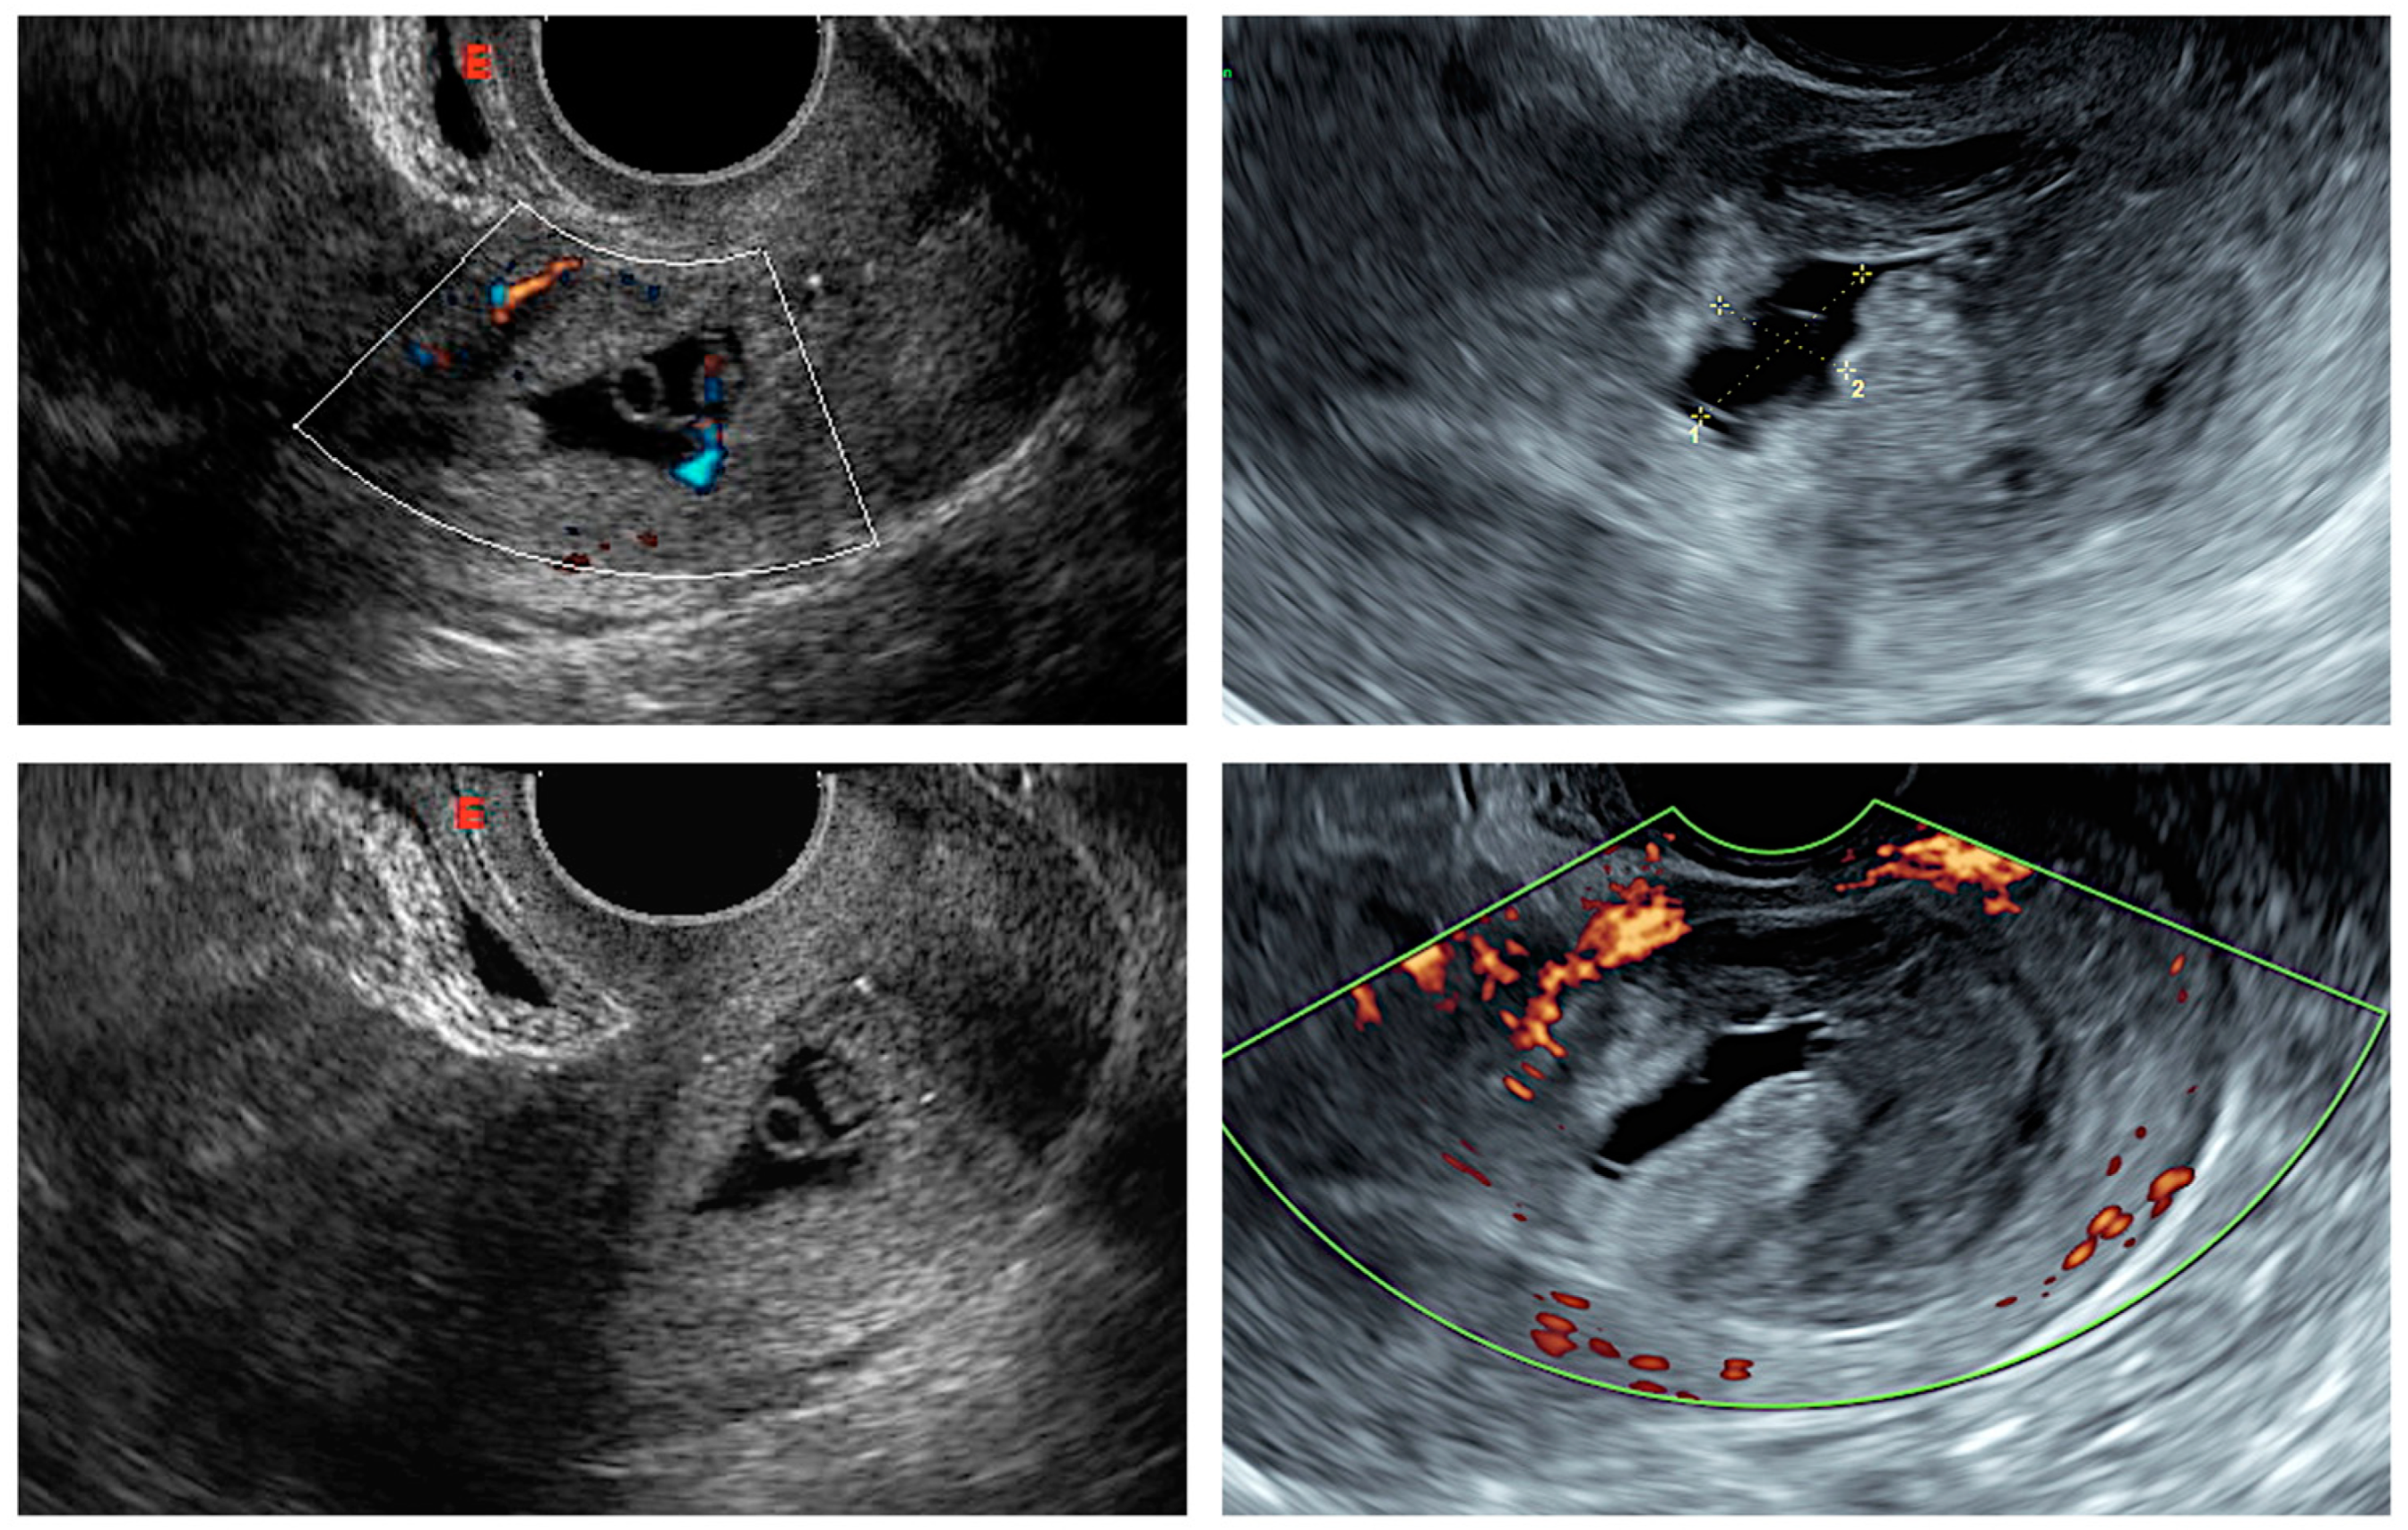

- the presence of a gestational sac, with or without fetal cardiac activity, embedded and surrounded by the myometrium, in the anterior part of the uterine isthmus (Figure 1);

- peritrophoblastic blood flow surrounding the CSP appearing on Doppler flow sonography.